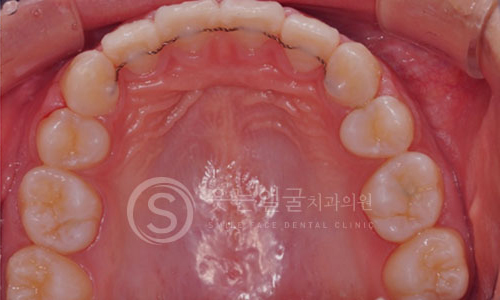

고난이도 임플란트

뼈 이식이나 발치 즉시 식립 등 까다로운 조건에서도 정밀 진단과

체계적인 시술 시스템으로 환자 맞춤형 치료를 제공합니다.

• 풍부한 임상 경험과 맞춤 진단

다양한 케이스에서 축적된 풍부한 임상 경험을

토대로, 환자별 구강 상태를 세밀하게 분석하여

최적의 임플란트 수술을 제공합니다.